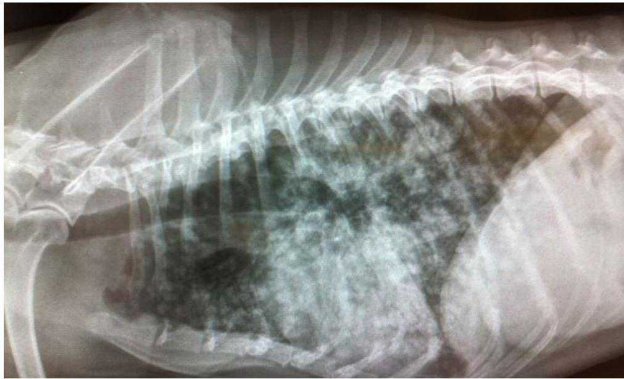

La diagnosi definitiva delle neoplasie surrenaliche, necessita purtroppo una valutazione istologica. Gli aspetti clinici, i dosaggi ormonali e i riliev di diagnostica per immagini possono ovviamente indirizzare verso un incidentaloma non secernente, un tumore secernente adrenocorticale, un feocromocitoma o una metastasi. Tuttavia la conferma definitiva richiede una biopsia. L’esame citologico ha dimostrato una elevata accuratezza nella distinzione di neoplasie corticali VS midollari. Ma quando è rischioso farlo?

L’esame citologico delle neoformazioni surrenaliche d’altra parte ha dimostrato una elevata accuratezza (90-100%) nella distinzione tra proliferazioni corticali (imagine in alto) e midollarii-feocromocitoma (immagine in basso). Sebbene non permetta con certezza di differenziarne forme maligne da benigne, il conoscere anticipatamente se una neoplasia sia corticale o midol

lare, permette al clinico di prendere possibili precazioni in caso di chirurgia, che potrebbe scatenare crisi ipertensive nel caso di un feocromocitoma.